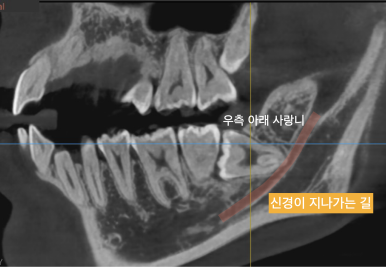

우측 위의 사랑니는 앞쪽 치아에 완전히 걸려있었고 (좌측 사진), 우측 아래의 사랑니는 신경관과 딱 닿아있었네요.. (우측 사진)